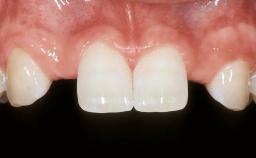

In this video Dr. Nikos Mattheos demonstrates the full diagnostic, planning and treatment sequence of an immediate implant with an immediate prefabricated provisional restoration in the esthetic zone. A 28 years old female patient presents with discoloration and increasing mobility of tooth 11. Advanced stage of external resorption is diagnosed. Patient's high esthetic demands combined with intact gingival architecture and periodontal health makes her a good candidate for immediate placement and restoration to preserve the gingival contour. Surgical and restorative treatment is planned with digital workflow based on data from CBCT and intraoral scan. An immediate temporary crown is manufactured for placement at the day of the surgery. Flapless extraction is performed, and the implant placed with guided surgery. Consequently, the buccal gap of the socket is augmented with Xenograft, while the soft tissue space maintained with a collagen plug. Finally, a provisional crown is immediately placed on the implant with a titanium temporary abutment and an emax prefabricated crown.

Papilla Complete

Recession Absent

Interproximal attachment At CEJ

Gingival display at full smile Medium

Shape of tooth crowns Triangular

Restorative status of neighboring teeth Virgin

Gingival Phenotype Medium-scalloped, medium-thick

Bone level on adjacent teeth 5.5 to 6.5 mm to contact point